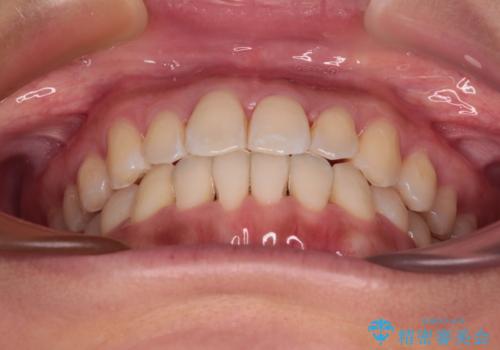

装着時間を守ってくださったので、予定通りの期間で終えることができました。インビザライン特有の、奥歯の咬み合わせの問題もなく、しっかりと歯列を改善することができました。